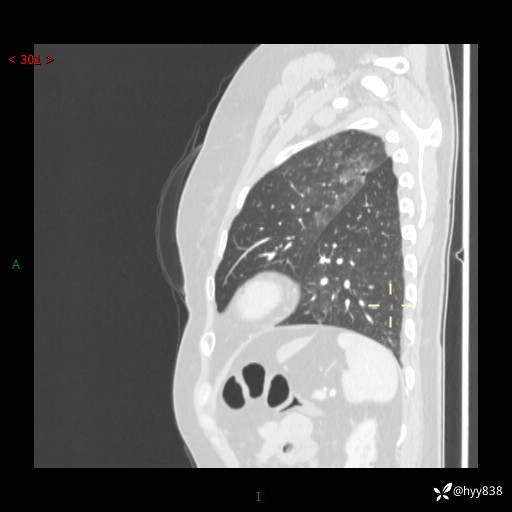

老年女性,偶然发现肺结节10天。结节不大,空洞不小,还牵拉胸膜---结果公布~

胸部CT增强(2024.8.2)